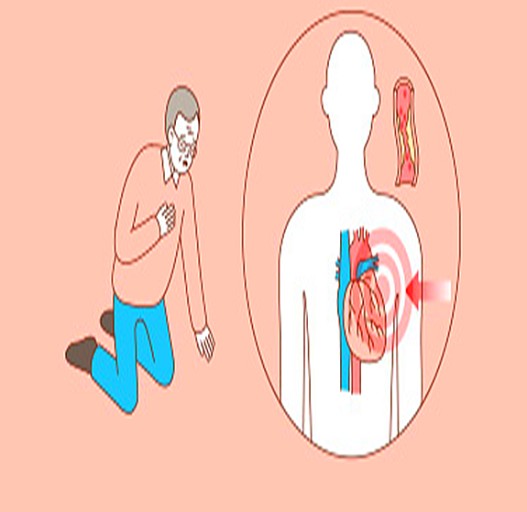

1. 쥐어짜는 듯한 가슴 통증 (흉통)

심근경색의 가장 전형적인 증상입니다.

가슴 중앙 또는 왼쪽 가슴 부근에서 극심한 압박감, 조이는 느낌, 짓누르는 듯한 통증이 나타나며

5분 이상 지속되는 경우가 많습니다. 통증은 휴식으로 사라지지 않고 점점 심해지기도 합니다.

심근경색 초기증상 2. 통증의 방사 – 팔, 어깨, 턱, 등으로 퍼지는 통증

가슴 통증이 왼쪽 팔, 어깨, 턱, 목, 등으로 퍼지는 경우는 심근경색 가능성이 매우 높습니다.

특히 왼팔 전체 또는 새끼손가락까지 저리거나 무거운 통증이 지속되면 즉시 병원을 방문해야 합니다.3. 갑작스런 식은땀

운동도 하지 않았는데, 차가운 땀이 주르륵 흐르듯 나타난다면 이는 매우 위험한 경고 신호입니다.

심장 혈류가 막히는 순간, 몸이 위급 상황으로 인식하여 자율신경 반응으로 식은땀을 흘리게 됩니다.

심근경색 초기증상 4. 극심한 호흡곤란

갑자기 숨이 막히거나 가슴이 답답해 숨을 쉬기 힘든 상태가 되며, 특히 누워있을 때 더 심해지는 경우도 있습니다.

숨이 차면서 공포심, 불안감까지 동반되면 심근경색 가능성을 고려해야 합니다.5. 속이 메스껍고 구토 또는 소화불량

이는 심정지로 이어지는 응급 상황일 수 있으므로 즉시 119 또는 응급실로 이동해야 합니다.심근경색 주의사항